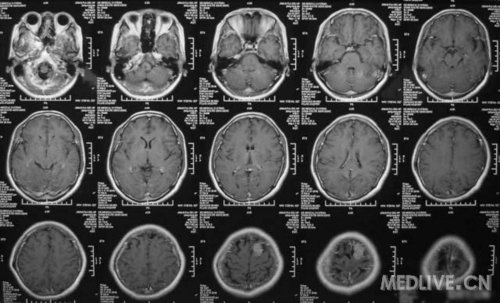

患者女,56岁,因右侧肢体活动不利2天于2011-06-15入院。查体:神志清,精神可,右侧肢体肌力4级,余无阳性体征。CT示左额叶占位,脑膜瘤可能性大。MRI示左额镰旁脑膜瘤,脑干左半亚急性梗塞。给予活血、神经营养、对症治疗,现一般情况好。请高手指点,何时手术切除脑膜瘤好啊?